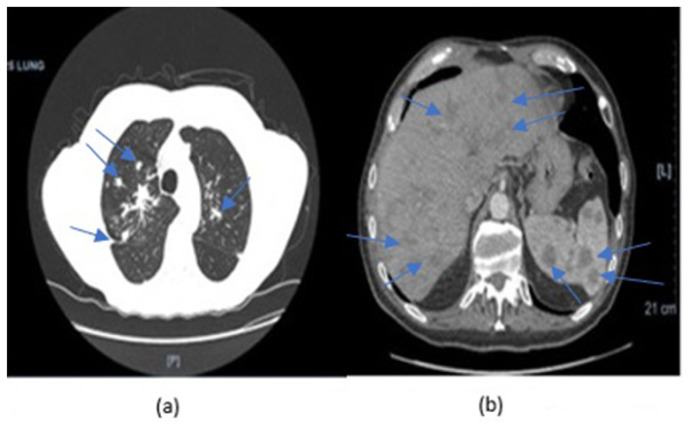

We report a 69-year-old with a past medical history of prostate cancer, and arsenic poisoning, who was incidentally found to have multiple pulmonary nodules and hepatosplenic lesions on CT imaging. He denied respiratory symptoms, but was noted to have significant weight loss. A bronchoscopy revealed mycobacterium kumamotonense on culture. He was treated presumptively for pulmonary and disseminated infection with azithromycin and ethambutol for 16 months, and 12 months of rifabutin after four months of rifampin which was discontinued due to resistance. Patient's weight loss resolved and CT imaging appeared significantly improved.